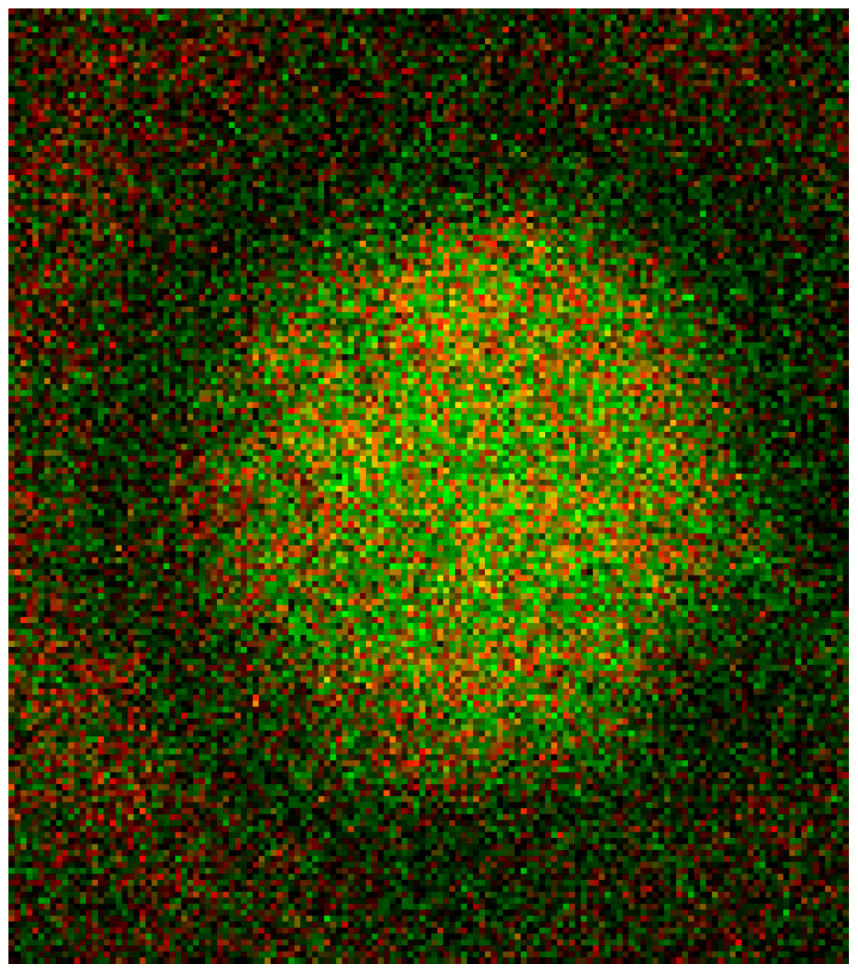

The merger of red (actin) and green (spectrin) channels of the confocal microscope revealed that the spectrin-/actin-distribution in singularized erythrocytes differed from the distribution in aggregated discocytes (see Figure 5). As main aspect in aggregated erythrocytes spectrin appeared to be the more or less homogeneously distributed over the whole cell (see Figure 5C), whereas in singularized erythrocytes the red stained actin in central parts of cells was a noticeable aspect (see Figure 5B).

Figure 5. Merger of red (actin) and green (spectrin) channels of the confocal microscope showing erythrocytes after examination in autologous plasma (AC) with details of magnified single (B) or aggregated erythrocytes (C) (reprinted from reference [20], Copyright 2013, with permission from IOS Press) (A) primary magnification 1:63; zoom factor 2.5; (B) primary magnification 1:63; zoom factor 5; (C) primary magnification 1:63; zoom factor 5.